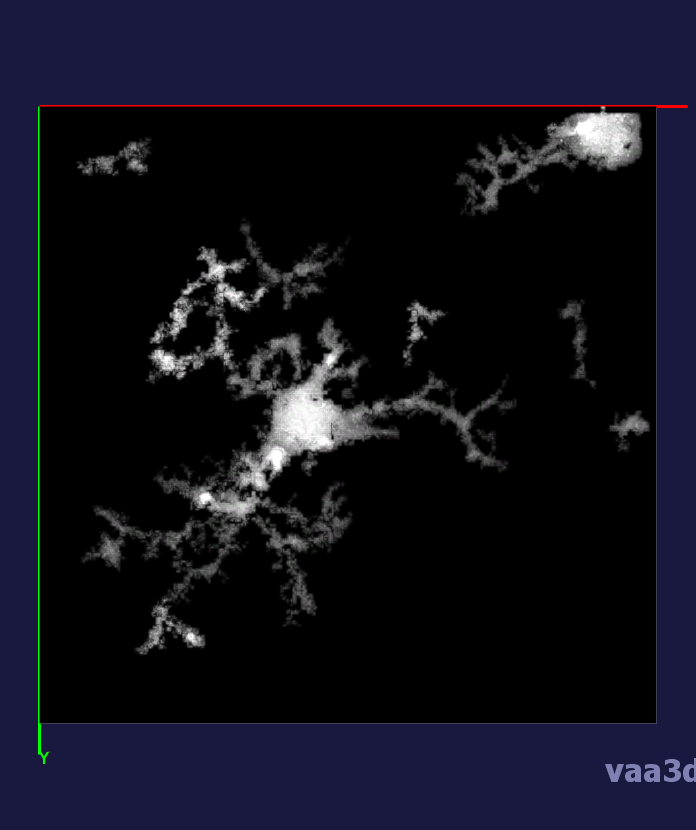

In our experiments, we compare the coupled TuFF-BFF microglia segmentation results with those given by L2S [21] and the Chan-Vese segmentation method [22]. The groundtruth in 3D was attained by manually tracing the object slice by slice from the z-stack. It must be noted that this was done by eye and could have some error. Figure 2 shows the visual comparison of the segmentation results for our dataset. Our result shown on the third column captures both the soma and processes. Figure 3 shows the Dice coefficient comparison of each segmentation method to the ground truth. Since the soma is much larger than the fine processes in the microglia, the processes have less volumetric impact on the similarity score. As explained in Section 1, segmenting the processes is important for quantifying the extension from the soma and its volume of surveillance. We use the Dice coefficient to quantitatively compare the ramification by taking the convex hull of the resulting segmentation. The Dice coefficient is a similarity measure that is computed using with where is the ground truth and is the compared image.

From Figure 4, the average Dice score for coupled TuFF-BFF was 0.77, compared to 0.53 for L2S [21] and .58 for Chan-Vese [22]. It must be noted that L2S required manual user initialization for each 2D image in the stack. While the Chan-Vese method has automatic seed selection, our coupled TuFF/BFF method was the only method that was a true 3D segmentation algorithm. L2S could not consistently capture the entire processes due to the intensity inhomogeneity throughout the object and background noise. The Chan-Vese segmentation could capture the extensions of the processes but did not work well with noise and attained false positives in the reconstruction. Since our method uses the tubular and blob information of the object to separate foreground and background, the segmentation only evolved within the object boundaries.